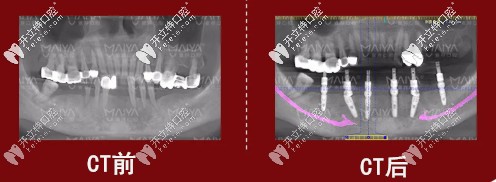

種植前后對比圖

種植牙前后對比圖